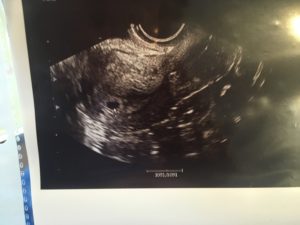

Плодное яйцо 8 мм не видно эмбриона

При проведении самого первого ультразвукового исследования, которое делается при задержке месячных и для того, чтобы диагностировать точно наличие маточной беременности, можно рассмотреть плодное яйцо.

Именно когда врач видит на мониторе это миниатюрное образование, он уже сообщает женщине, что она скоро станет мамой. На мониторе можно рассмотреть плодное яйцо, которое представляет собой небольшое образование овальной формы.

На ранних сроках эмбрион, который в дальнейшем будет развиваться и расти в плодном яйце, не визуализируется еще, однако скоро он подрастет, и тогда его уже можно будет хорошо рассмотреть.

Эмбрион зачастую виден уже с пятой недели беременности, однако иногда бывают случаи, когда и на данном сроке врач на ультразвуковом исследовании не видит эмбрион, в такой ситуации назначается повторное УЗИ.

Очень часто повторный ультразвук показывает и эмбрион, и его сердцебиение. Когда после шести-семи недель не виден эмбрион, тогда, к сожалению, высок риск того, что не развивается беременность. В этой статье мы рассмотрим нормы плодного яйца по неделям.